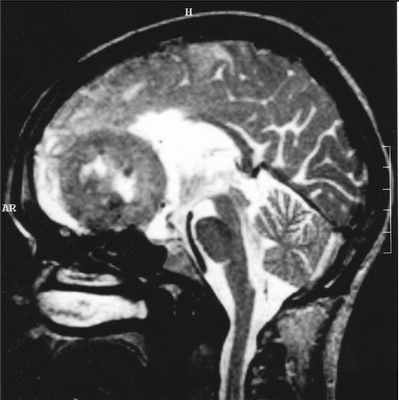

МРТ головного мозга. Менингиома свободного края намета мозжечка (область шишковидной железы). Сагиттальные Т1-зависимые МРТ до и после контрастирования.

Менингиома может развиться из любого участка стенки задней черепной ямки, но чаще из свободного края намета мозжечка и в области большого затылочного отверстия. Эти менингиомы при МРТ головного мозга имеют те же черты, что и характерные для супратенториальных менингиом. Дополнение стандартной МРТ МР-венографией помогает выявить компрессию поперечного синуса.